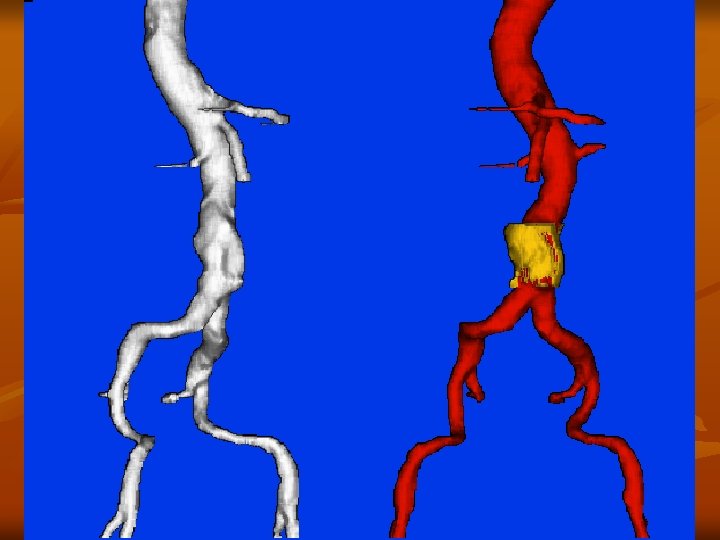

CTA methodika IV. képrekonstructio n n n Számítógépes munkaállomás Subtractio (prae- és posztkontrasztos kép) végezhető a képminőség javításához 2 D hatású rekonstructiok n n n MPR - Multi Planar Reconstruction MIP - Maximum Intensity Projection 3 D hatású rekonstructiok n Surface és volume rendering

A CTA leggyakoribb alkalmazása n Mellkasi és hasi aorta, valamint iliaca rendszer vizsgálata aneurysma esetén a CTA pontos választ ad: - nagyság – növekedés - kiterjedés – kiinduló erek érintettsége - trombotizáltság - ruptura fennállása – haematoma